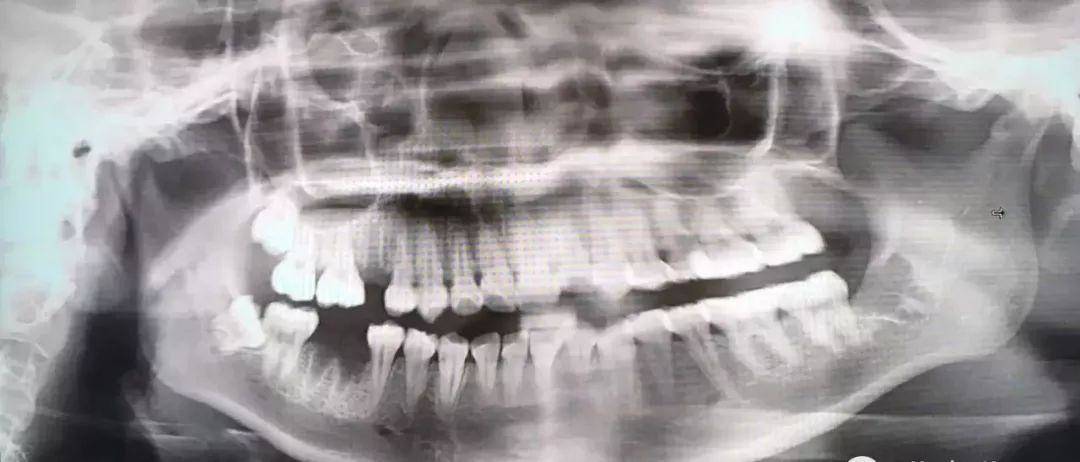

1.2 恰当检查 包括高质量的X线片,它不仅能提供牙齿的清晰图像,牙根的轮廓和解剖以及牙周骨质情况,还能提供牙齿与邻牙和其他结构之间的关系,其中尤其是下颌骨下缘、下颌骨升支以及下牙槽神经束之间的关系。

2.2 术前评价 在有下牙槽神经损伤可能性时,应该通过术前的放射片来评价下牙槽神经损伤的风险是低、中、高或非常高,给患者的警告应能体现这种评价结果。